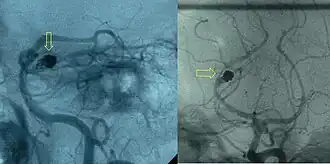

Arteriogram showing a partially coiled aneurysm (indicated by yellow arrows) of the posterior cerebral artery with a residual aneurysmal sac. The person was a 34-year-old woman initially treated for a subarachnoid hemorrhage.

If a cerebral aneurysm is identified on angiography, two measures are available to reduce the risk of further bleeding from the same aneurysm: clipping[56] and coiling.[57] Clipping requires a craniotomy (opening of the skull) to locate the aneurysm, followed by the placement of clips around the neck of the aneurysm. Coiling is performed through the large blood vessels (endovascularly): a catheter is inserted into the femoral artery in the groin and advanced through the aorta to the arteries (both carotid arteries and both vertebral arteries) that supply the brain. When the aneurysm has been located, platinum coils are deployed that cause a blood clot to form in the aneurysm, obliterating it. The decision as to which treatment is undertaken is typically made by a multidisciplinary team consisting of a neurosurgeon, neuroradiologist, and often other health professionals.[4]

In general, the decision between clipping and coiling is made on the basis of the location of the aneurysm, its size and the condition of the person. Aneurysms of the middle cerebral artery and its related vessels are hard to reach with angiography and tend to be amenable to clipping. Those of the basilar artery and posterior cerebral artery are hard to reach surgically and are more accessible for endovascular management.[58] These approaches are based on general experience, and the only randomized controlled trial directly comparing the different modalities was performed in relatively well people with small (less than 10 mm) aneurysms of the anterior cerebral artery and anterior communicating artery (together the "anterior circulation"), who constitute about 20 percent of all people with aneurysmal SAH.[58][59] This trial, the International Subarachnoid Aneurysm Trial (ISAT), showed that in this group the likelihood of death or being dependent on others for activities of daily living was reduced (7.4 percent absolute risk reduction, 23.5 percent relative risk reduction) if endovascular coiling was used as opposed to surgery.[58] The main drawback of coiling is the possibility that the aneurysm will recur; this risk is extremely small in the surgical approach. In ISAT, 8.3 percent needed further treatment in the longer term. Hence, people who have undergone coiling are typically followed up for many years afterwards with angiography or other measures to ensure recurrence of aneurysms is identified early.[60] Other trials have also found a higher rate of recurrence necessitating further treatments.[61][62]